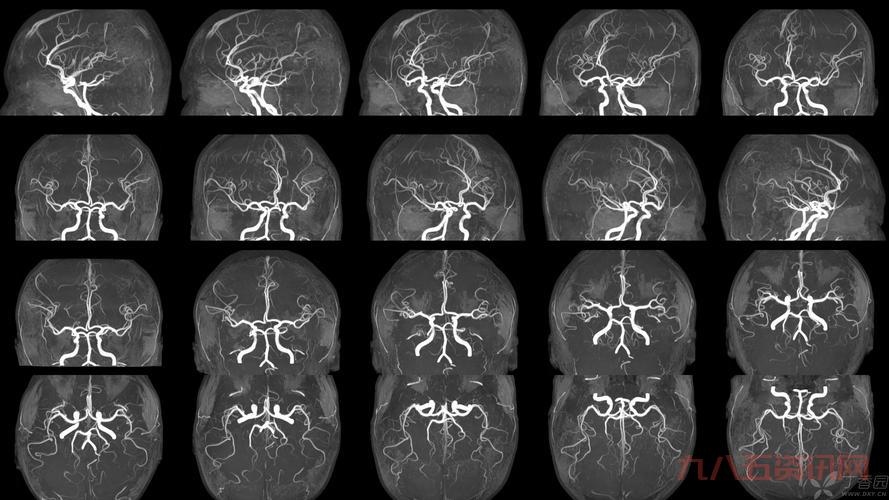

那天,我照常在家搞我的設備,突然就琢磨起這個“t2”到底是个起初我也不懂,就到處找資料,問人,可算是把“t2”是個啥弄明白。這玩意兒在醫學上還是核磁共振成像裡頭的一個關鍵指標,主要说的就是那個橫向磁化矢量恢復到一個平衡時狀態的時間,大概是這個意思。

- 像那個頸椎T2,說的就是在做核磁共振的時候,那個橫向磁化矢量衰減到最大值的百分之37所需要的時間。

- 還有那個T2信號影,就是說在核磁共振成像裡頭,組織在T2加權圖像上的表現。